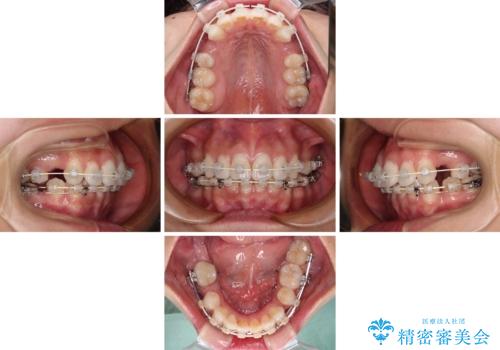

右下の埋伏歯はやはり癒着しており、抜歯の後にインプラントを埋入することとなりました。

埋伏歯の牽引や、奥歯の咬み合わせ改善、インプラント補綴治療と治療期間が延びてしまう要素が多く、治療は難航しましたが、最終的に非常に満足のいく仕上がりとなりました。